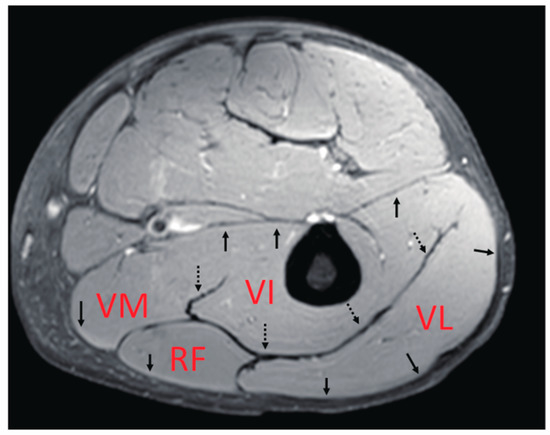

The main knee extensor is the quadriceps muscle. As the name suggests, this muscle includes the four heads of the muscle bellies of the vastus lateralis (VL), vastus medialis (VM), vastus intermedius (VI), and rectus femoris (RF). VL, VM, and VI are mono-articular muscles crossing one joint at the knee, while RF is a bi-articular muscle operating over two joints, including the hip and knee. In terms of their locations inside the thigh, only the VI, reported to contribute significantly to the generation of knee extension torque [4], is located in a deep position near the femur, while the others are more superficial. In addition, as summarized by Finni et al. [5], their fascicle architectures as an anatomical morphology of bundles of muscle fibers [6,7], as well as their fiber compositions [8,9], are quite complicated compared with those of the medial gastrocnemius, which has been thoroughly investigated. Thus, it is likely that these variations in the characteristics of each muscle generate differences in the contraction behavior of deformation, such as length change, thereby, significantly affecting the force generation function of these muscles. Furthermore, quadriceps muscles have thick well-developed common aponeuroses between muscles (Figure 1), within which force and deformation may be coupled, giving rise to the possibility of synchronized length changes at these junctions. However, detailed knowledge of the muscle deformation of separate quadriceps muscles during contraction is limited.

Figure 1. An example of the anatomical MR cross-sectional image of the center of the thigh. The quadriceps muscle includes the four heads of the muscle bellies of the vastus lateralis (VL), vastus medialis (VM), vastus intermedius (VI), and the rectus femoris (RF). The arrows show the aponeuroses surrounding the quadriceps muscle. The dotted arrows point to the thick aponeuroses referred to as “central aponeuroses” in this study.